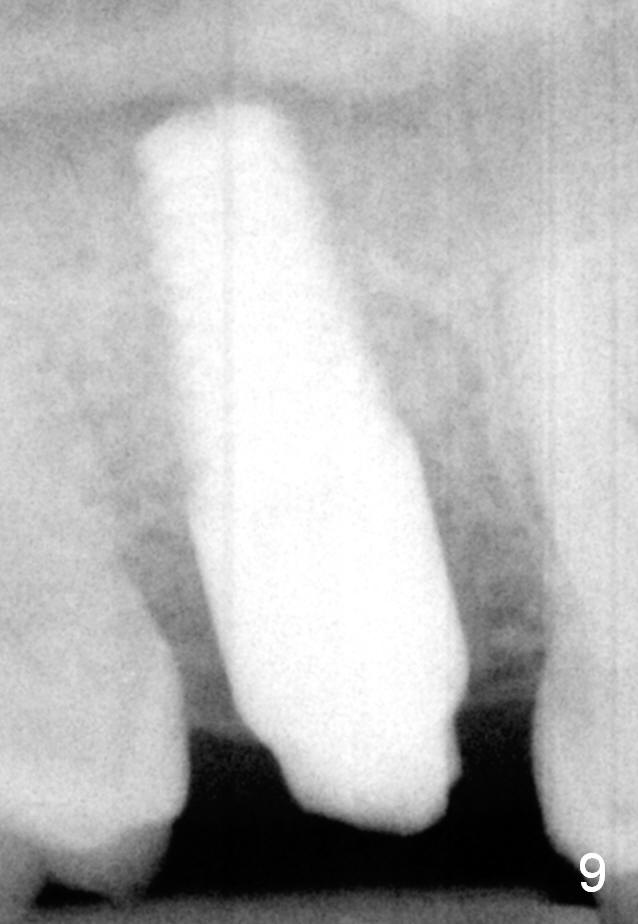

The implant remains stable 2.5 months postop without abnormal bone resorption (Fig.9). Since the provisional has dislodged on several occasions, impression is taken for final restoration. When the provisional is removed 3 months postop, the margin of the restoration is shown to be subgingival (Fig.10 arrowheads), but is distinctly separated from the gingiva. This is due to the presence of the provisional (its margin were fabricated slightly deeper). The provisional is also intentionally fabricated slightly larger than the final restoration. When the latter is cemented, there is space to remove extra cement trapped subgingivally (Fig.11). No cement is visible post cementation (Fig.12 (C: crown)). Eighteen months post cementation, the patient returns for recementation. After laser gingivectomy and Panavia resin bonding, PA shows residual cement (Fig.13 ^). After repeated removal with Piezo scaler and explorer, the residual cement appears to be smaller, which is ignored at the time of X-ray taking (Fig.14 ^). More dismayed is tight mesial contact. Water pik is recommended. When peri-implantitis develops later on, make an incision for cement removal. If the crown is dislodged soon, check whether the existing abutment is loose, remove acrylic in the access hole and remove the abutment. Install a new 4x3 mm one. Trim the abutment carefully and more on the opposing tooth.